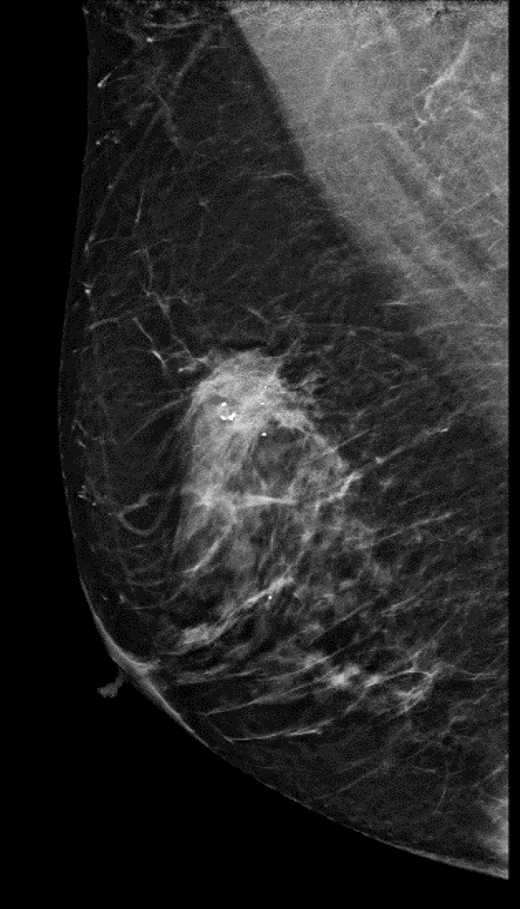

Mamografía. Proyección oblicua medio-lateral.